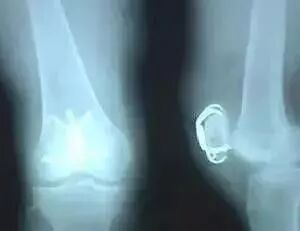

4、退化性关节炎

①在不知不觉中加剧的或逐渐的发作;

②早晨僵硬和疼痛;

③在站立的前后(AP)X光片的关节间隙变窄;

④角度畸形(变异的);

⑤渗出液;

⑥疼痛及压痛点在患部关节线(内侧及/或外侧);

⑦骨赘。